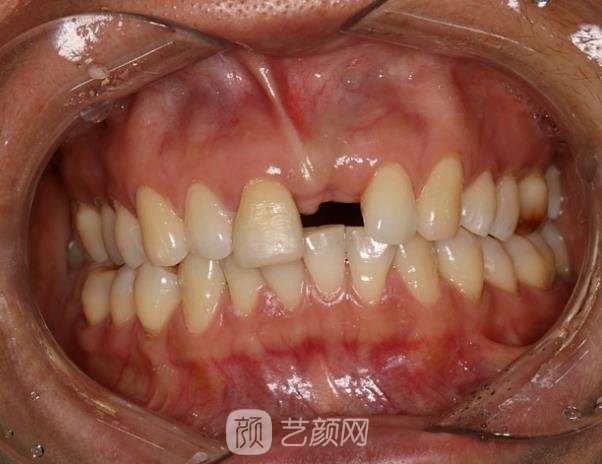

種植牙案例:

對(duì)于我這個(gè)年紀(jì)來(lái)說(shuō),種植牙其實(shí)并不適合我,畢竟沒(méi)有哪個(gè)人年紀(jì)輕輕就掉牙的,但我就是一個(gè)例外,一場(chǎng)意外導(dǎo)致我的牙掉了,當(dāng)時(shí)我心情壞到了極點(diǎn),畢竟缺了一顆牙,對(duì)誰(shuí)都不好受。

為了遮掩這個(gè)缺陷,我的笑容也減少了,幸好這段時(shí)間都戴口罩,我這個(gè)缺陷大家都看不見(jiàn),平時(shí)如果實(shí)在忍不住,都會(huì)用手進(jìn)行遮掩,所以大家都說(shuō)我變得含蓄內(nèi)向了,整個(gè)人的給人的形象發(fā)生了很大的變化。

為了回歸本性,我較終選擇了種植牙,當(dāng)時(shí)在一番了解后發(fā)現(xiàn),種植牙的價(jià)格蠻高,所以在選擇的時(shí)候尤為謹(jǐn)慎,較終我選擇當(dāng)?shù)氐暮D厢t(yī)學(xué)院第一附屬醫(yī)院,這家醫(yī)院的口腔科在當(dāng)?shù)刂群芨?,所以選擇這家我還是較為放心的。

慢慢的,種植牙部位的傷口也恢復(fù)好了,從外表看不出任何不同,牙齒完全沒(méi)有色差,看起來(lái)渾然一體,現(xiàn)在也可以放心大笑了,完全不用遮遮掩掩了,身邊的朋友都說(shuō)以前的我回來(lái)了。